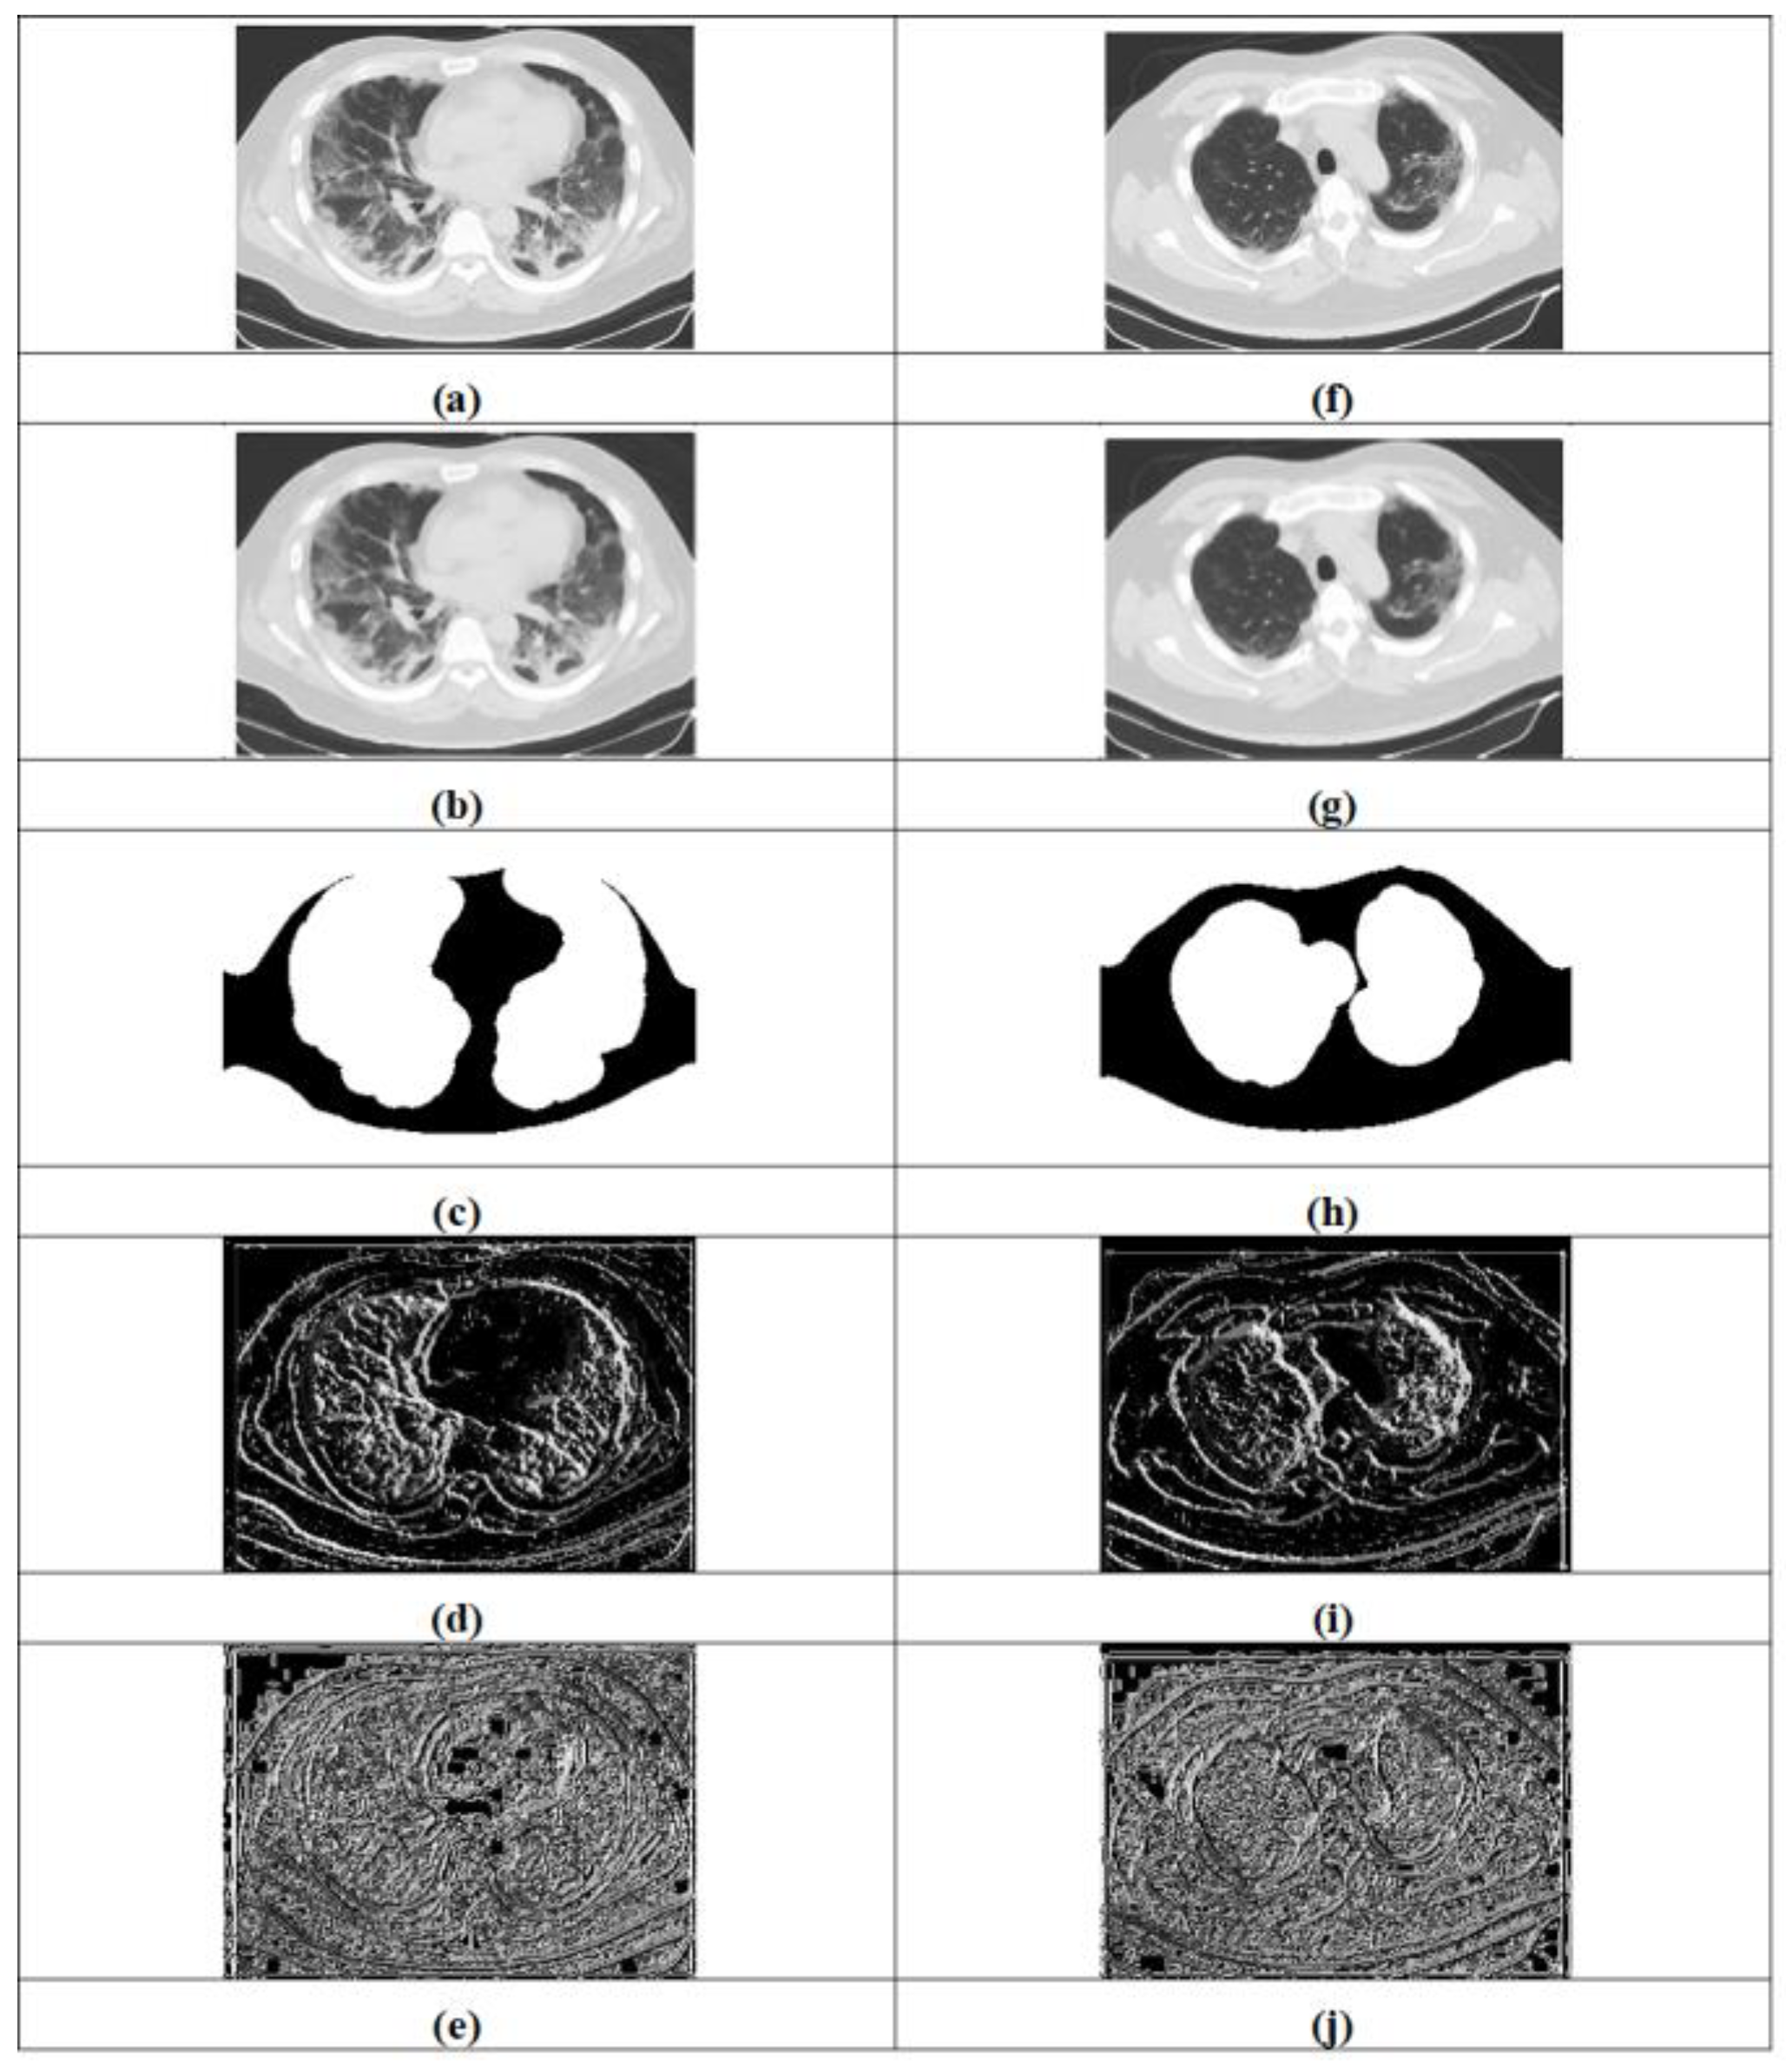

3.1. Acquisition of Input Image

3.2. Image Pre-Processing Using Adaptive Wiener Filtering and ROI Extraction

3.2.2. ROI Extraction

3.3. Lung Lobe Segmentation Using PSP-Net

4.2. Description of Dataset